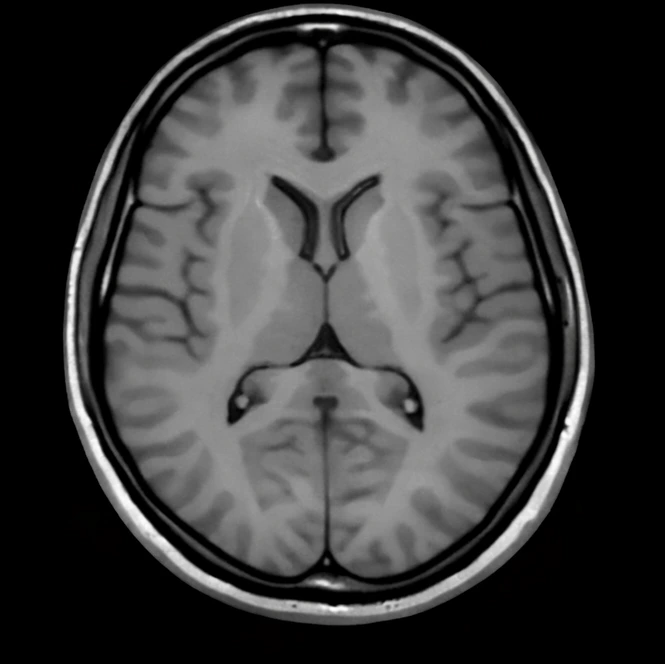

Accelerate diagnosis with super-resolution tools that highlight subtle anomalies and improve scan clarity.

Empower professionals with side-by-side AI comparisons and enhanced anatomical visualizations.

Visualize and quantify complex volumetric datasets for longitudinal studies and breakthrough discovery.